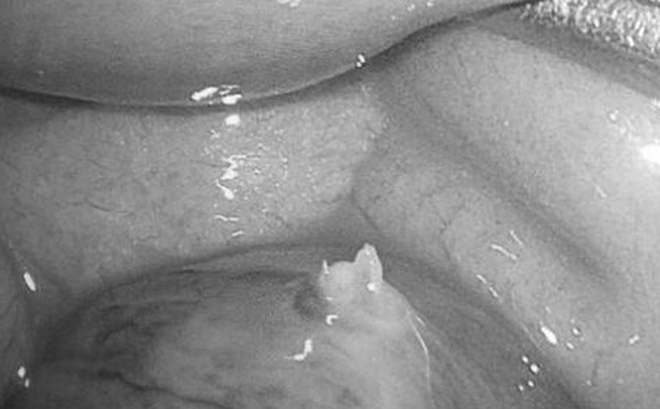

Ruột non của bệnh nhân bị tổn thương do xương cá đâm thủng

Qua thăm khám, bác sĩ nghi ngờ bụng ngoại khoa. Sau khi hội chẩn cùng các bác sĩ Khoa Ngoại Tiêu hóa, bệnh nhân được cho chụp MSCT bụng. Kết quả cho thấy bệnh nhân bị thủng ruột non vị trí bụng dưới lệch trái do dị vật cản quang kích thước # 2 x 28 mm, nghi xương cá.

Quá trình phẫu thuật, các bác sĩ ghi nhận ổ bụng của bệnh nhân U. có dị vật xương cá đâm thủng ruột non, viêm túi thừa ruột non nên đưa ra hướng xử trí là lấy xương cá, khâu lỗ thủng ruột non, cắt túi thừa ruột non. Sau phẫu thuật, tình trạng bệnh nhân dần hồi phục và đã xuất viện.